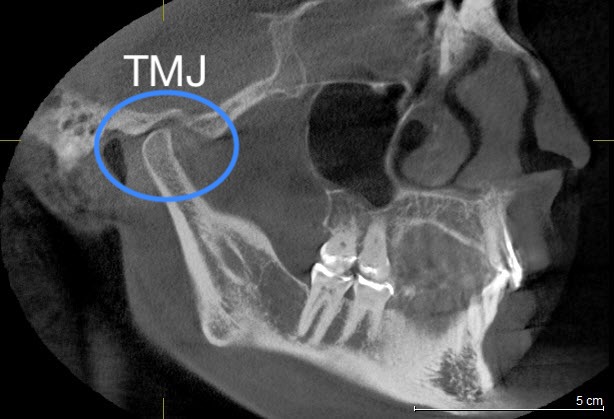

The major component of diagnosis in our office is cone-beam CT (CBCT) analysis, Jaw Tracking, Transcutaneous Electrical Neural Stimulation (TENS), Electromyograph (EMG), and Jaw Joint Sonograph. These instruments have been used for years in medical specialties and are now being used in dentistry to measure postural balance and muscle dysfunction of the jaw, which is the major culprit in the majority of patients reporting headache profiles.